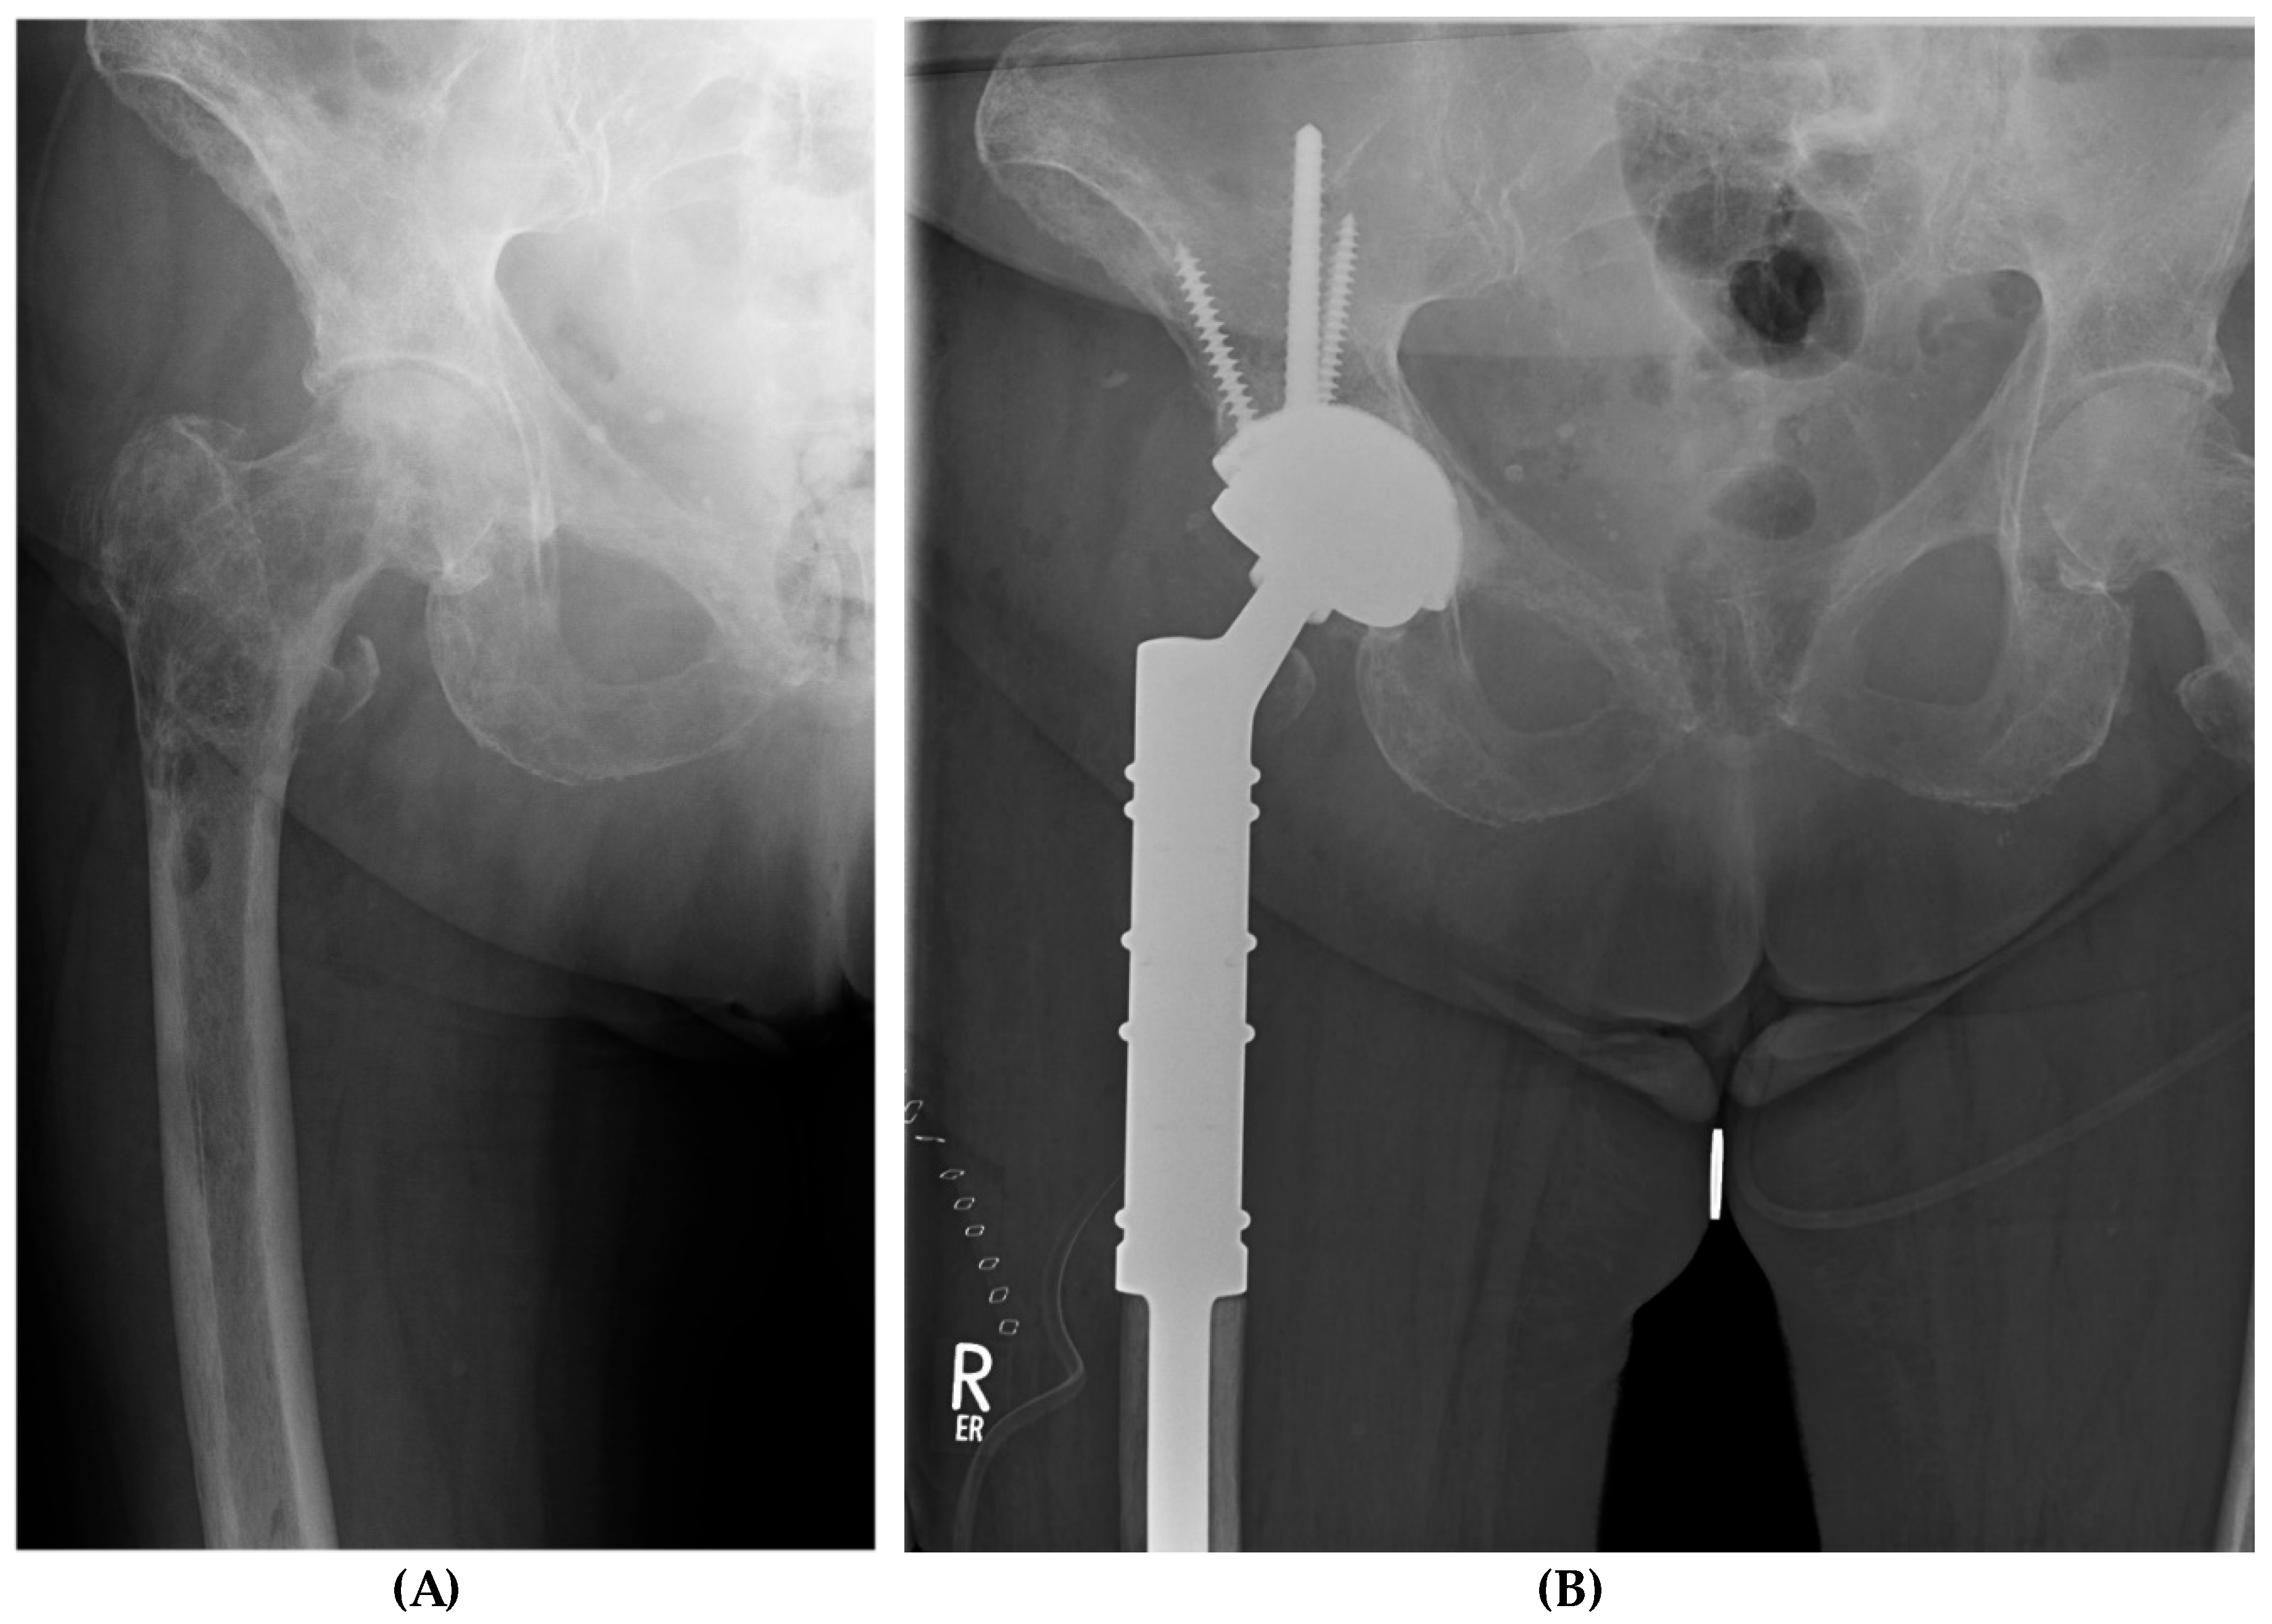

The Modified Harrington Procedure for Metastatic Peri-Acetabular Bone Lesion Using a Novel Highly Porous Titanium Revision Shell with Long Lever Arm Screw

2.2. Surgical Procedure